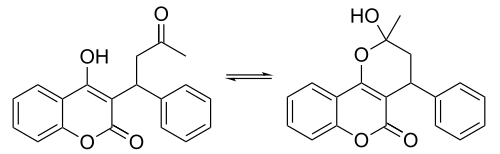

Chemistry

X-ray crystallographic studies of warfarin show that it exists in tautomeric form, as the cyclic hemiketal, which is formed from the 4-hydroxycoumarin and the ketone in the 3-position substituent.[79] However, the existence of many 4-hydroxycoumadin anticoagulants (for example phenprocoumon) that possess no ketone group in the 3-substituent to form such a structure, suggests that the hemiketal must tautomerise to the 4-hydroxy form in order for warfarin to be active.[80]